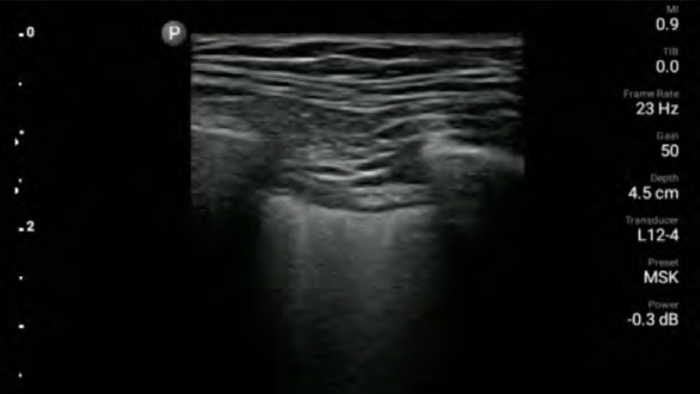

Verminder complicaties tijdens naaldgeleide procedures

De Lumify draagbare echografieoplossing voor loco regionale anesthesiologie helpt u bij het visualiseren van de omliggende zenuwen, vaten, omliggende weefsels en naald-in situ tijdens de procedure.